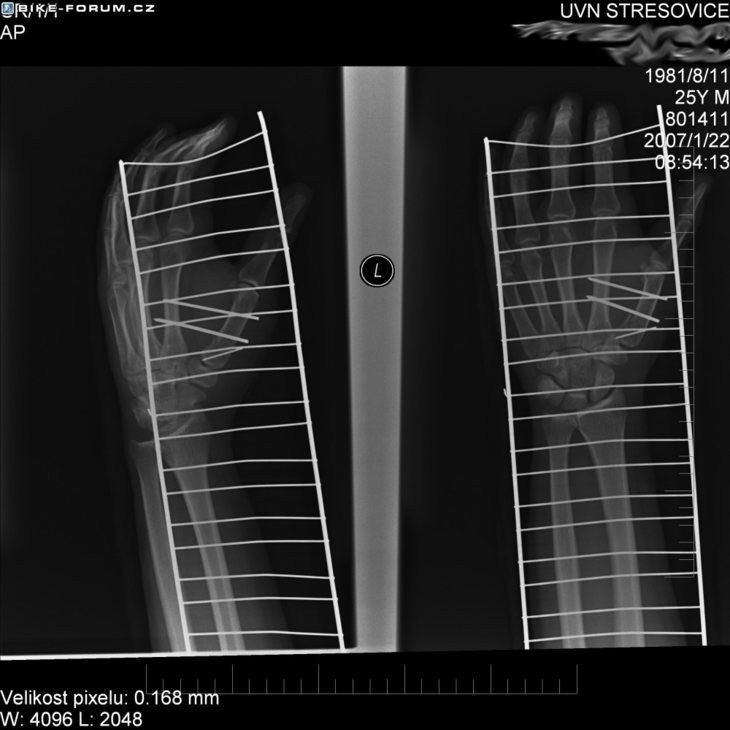

Lava ruka - zlomeny palec

to iste ako predchadzajuci obr.

to je dlaha vole

Co je ta mrizka? To vypada, jako bys ji mel na grilu :-) Ba ne, neni to k smichu, ale ja nikdy nic zlomeneho nemel, tak se ptam. Jinak preji brzke uzdraveni..